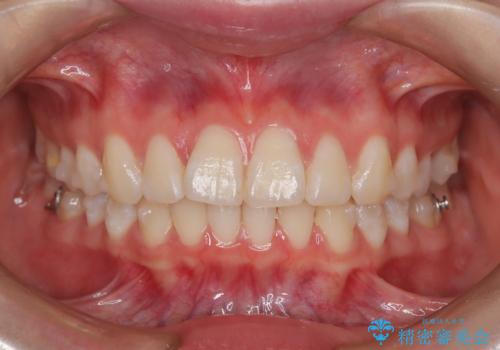

前歯のガタつきを治したい 翼状捻転マウスピース矯正

- 上顎前歯の突出、がたつき(翼状捻転)を主訴に来院されました。当院では総合歯科医療が可能であるため、矯正前処置として虫歯治療・歯周治療、親知らず抜歯を施行しました。その後、非抜歯かつ口元が出ないようなマウスピース治療を行いました。仕事柄、1日の装着時間が短くなってしまう時期もありましたが、患者様と相談しながら問題なく終了しています。